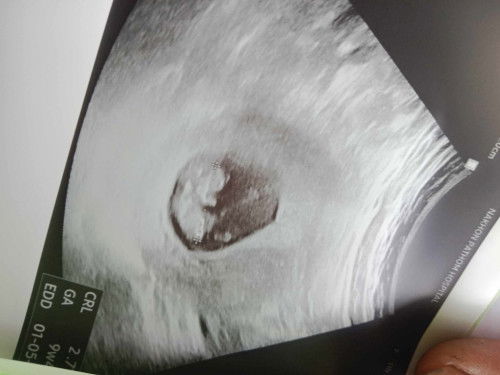

อยากทราบว่าแม่ๆคิดว่ากี่เดือนค่ะ

ตอนนี้ตั้งครรภ์ได้2เดือนกว่ามีพี่ๆที่ทำงานขอดูรูปอัลตราซาวเขาบอกว่าไม่น่าใช่2เดือนกว่าจริงไหมค่ะแล้วแม่ๆคิดว่ากี่เดือนค่ะรูปนี้#ขอคำแนะนำกับแม่ๆด้วยนะคะ

9วีค4วัน=2เดือน1สัปดาห์4วันค่ะ